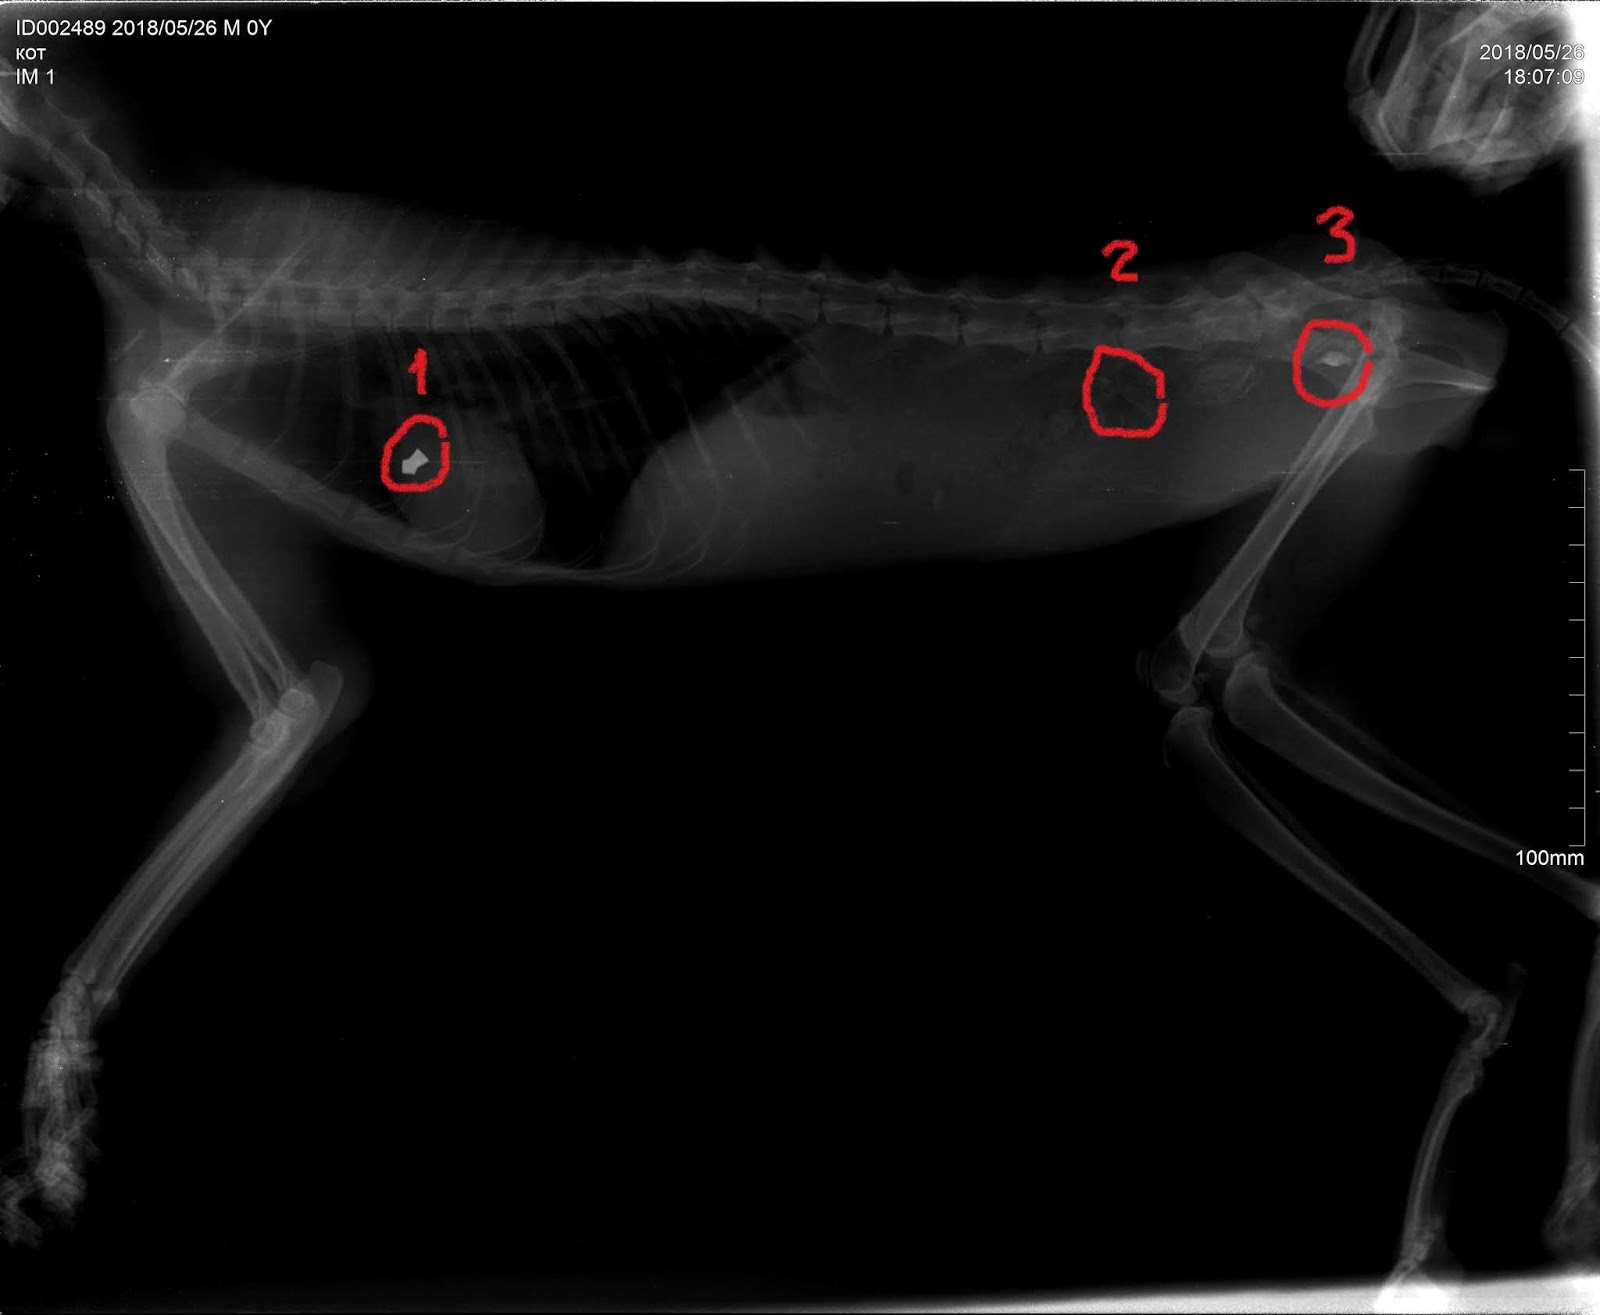

Сердце кошек находится в грудной полости, немного смещено влево от середины. Оно расположено между легкими и защищено грудиной. Обычно сердце кошки располагается на уровне позвоночника в области предплечий.

Несмотря на то, что наружу сердце кошек не видно, с помощью некоторых методов изображение его местоположения можно получить. Фотографии представленные в статье позволят вам визуализировать и понять, где именно находится сердце у кошек.

Просмотрите фотографии ниже и узнайте, где у кошек находится сердце: